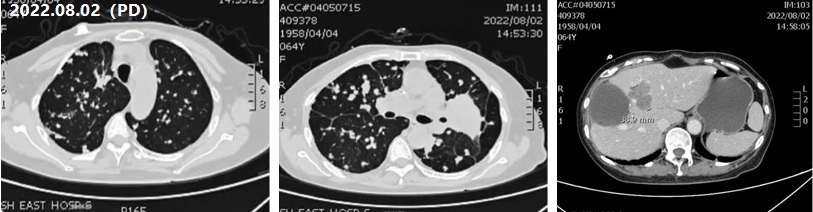

五线治疗(2022年6月——2022年7月底)

治疗评估:鉴于患者化疗后再次PD,后线治疗缺少更优方案,仍继续使用四线治疗方案;

治疗方案:贝伐珠单抗联合FOLFORI方案;

疗效评估:2022年8月2日,患者肺部及肝脏病灶再次出现增多增大,提示PD;

图5 五线治疗CT影像评估